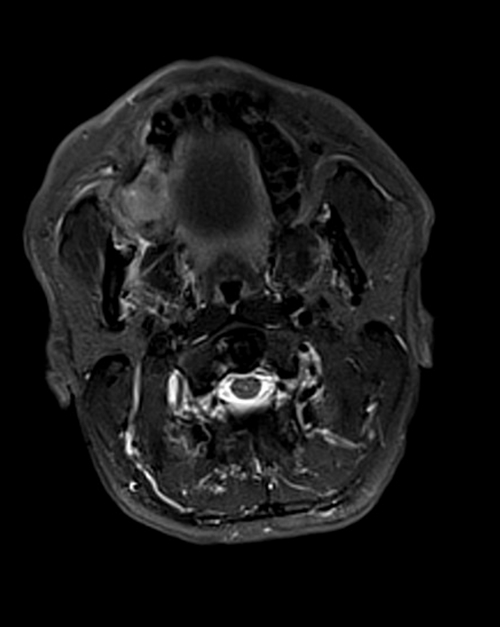

- МРИ височно-нижнечелюстного сустава